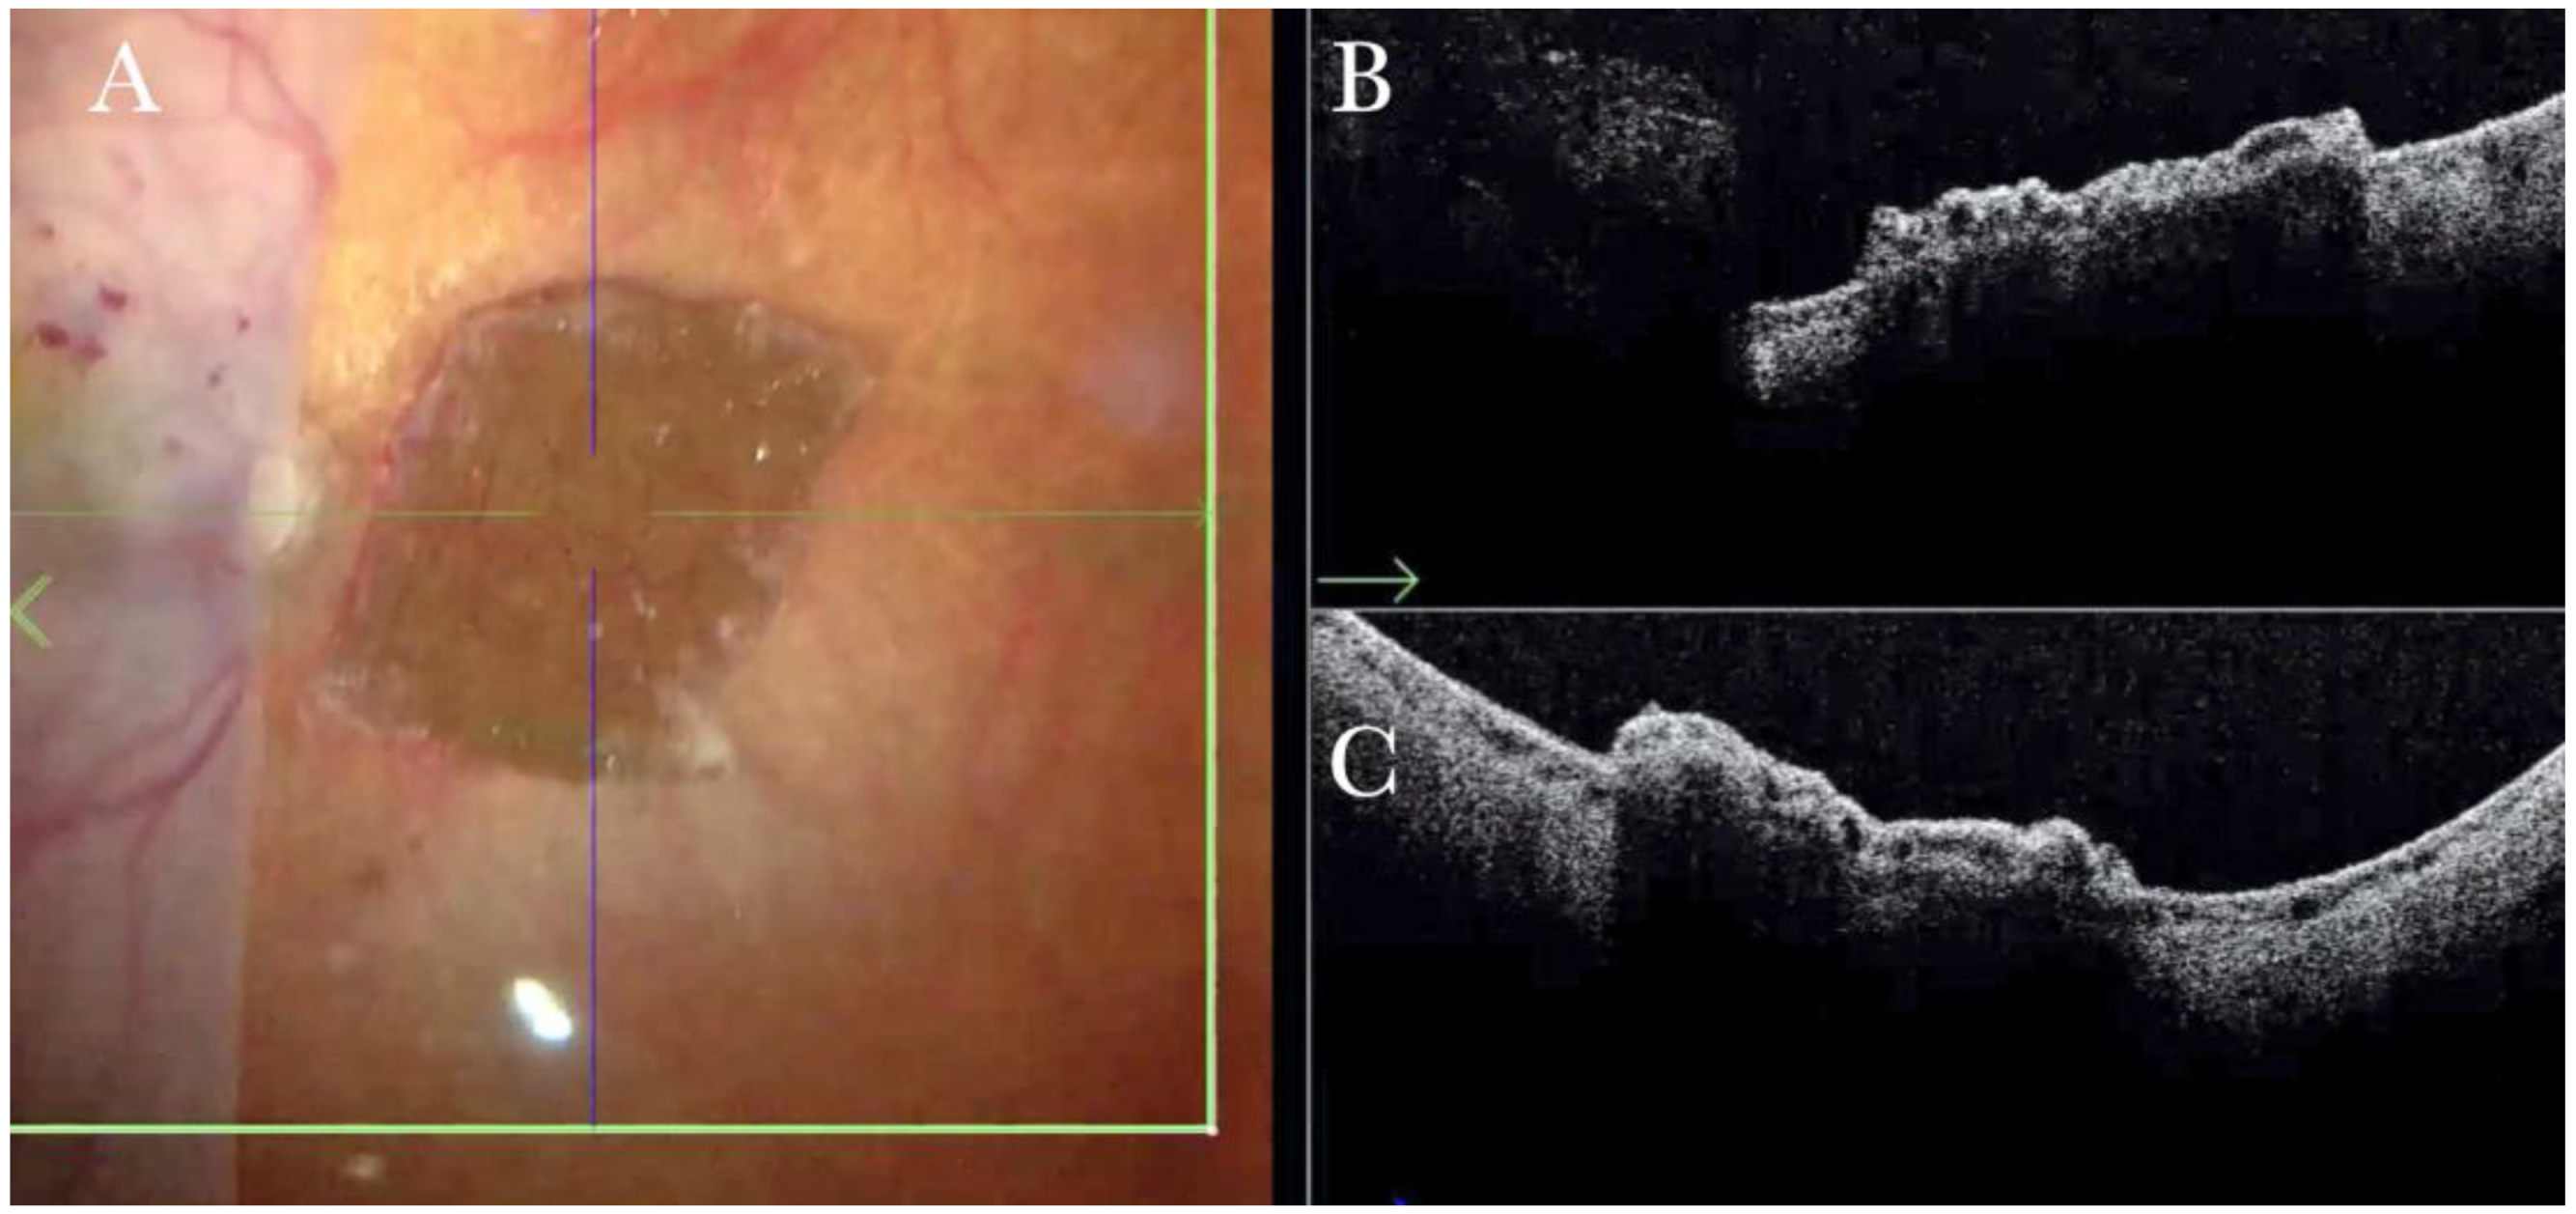

Figure 4.

(A) Microscope view of the macular area during peeling of an epiretinal membrane (ERM). The ERM is elevated. (The white box indicates the field-of-view of the OCT scan, the green circle within the white box represents the effective working distance and green and blue lines within the green circle show the vertical and horizontal scan planes). (B) Intraoperative optical coherence tomography (i-OCT) B horizontal (green arrow) scan during peeling. The ERM is elevated, and the macular profile is preserved where the ERM has been peeled. (C) i-OCT B vertical (blue arrow) scan during peeling. The ERM is elevated. The inner limiting membrane (ILM) is stretched and elevated where the ERM is peeled. The i-OCT allowed us to see the double simultaneous peeling of ERM and ILM.